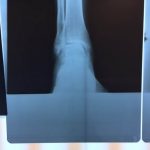

Ten years of severe ankle pain with a mal-positioned ankle fusion is now relieved! Patient is now walking with pain-free ankle motion!